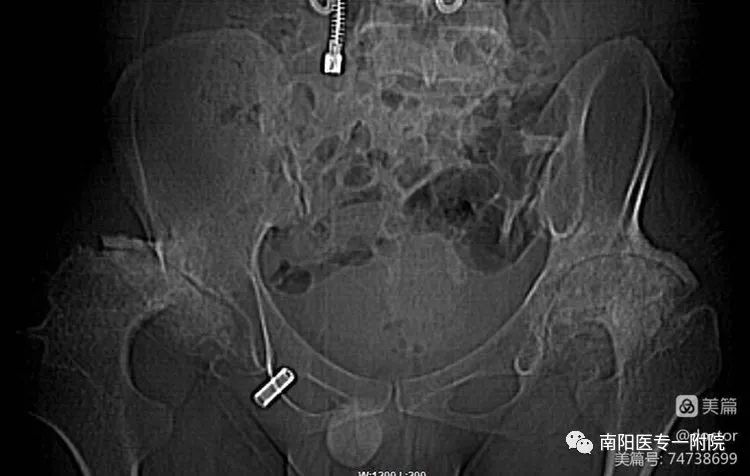

右侧股骨头大部缺失,关节边缘多发骨质增生